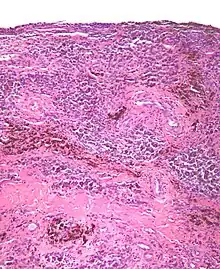

| Micrograph of diffuse TGCT, also known as pigmented villonodular synovitis. H&E stain. | |